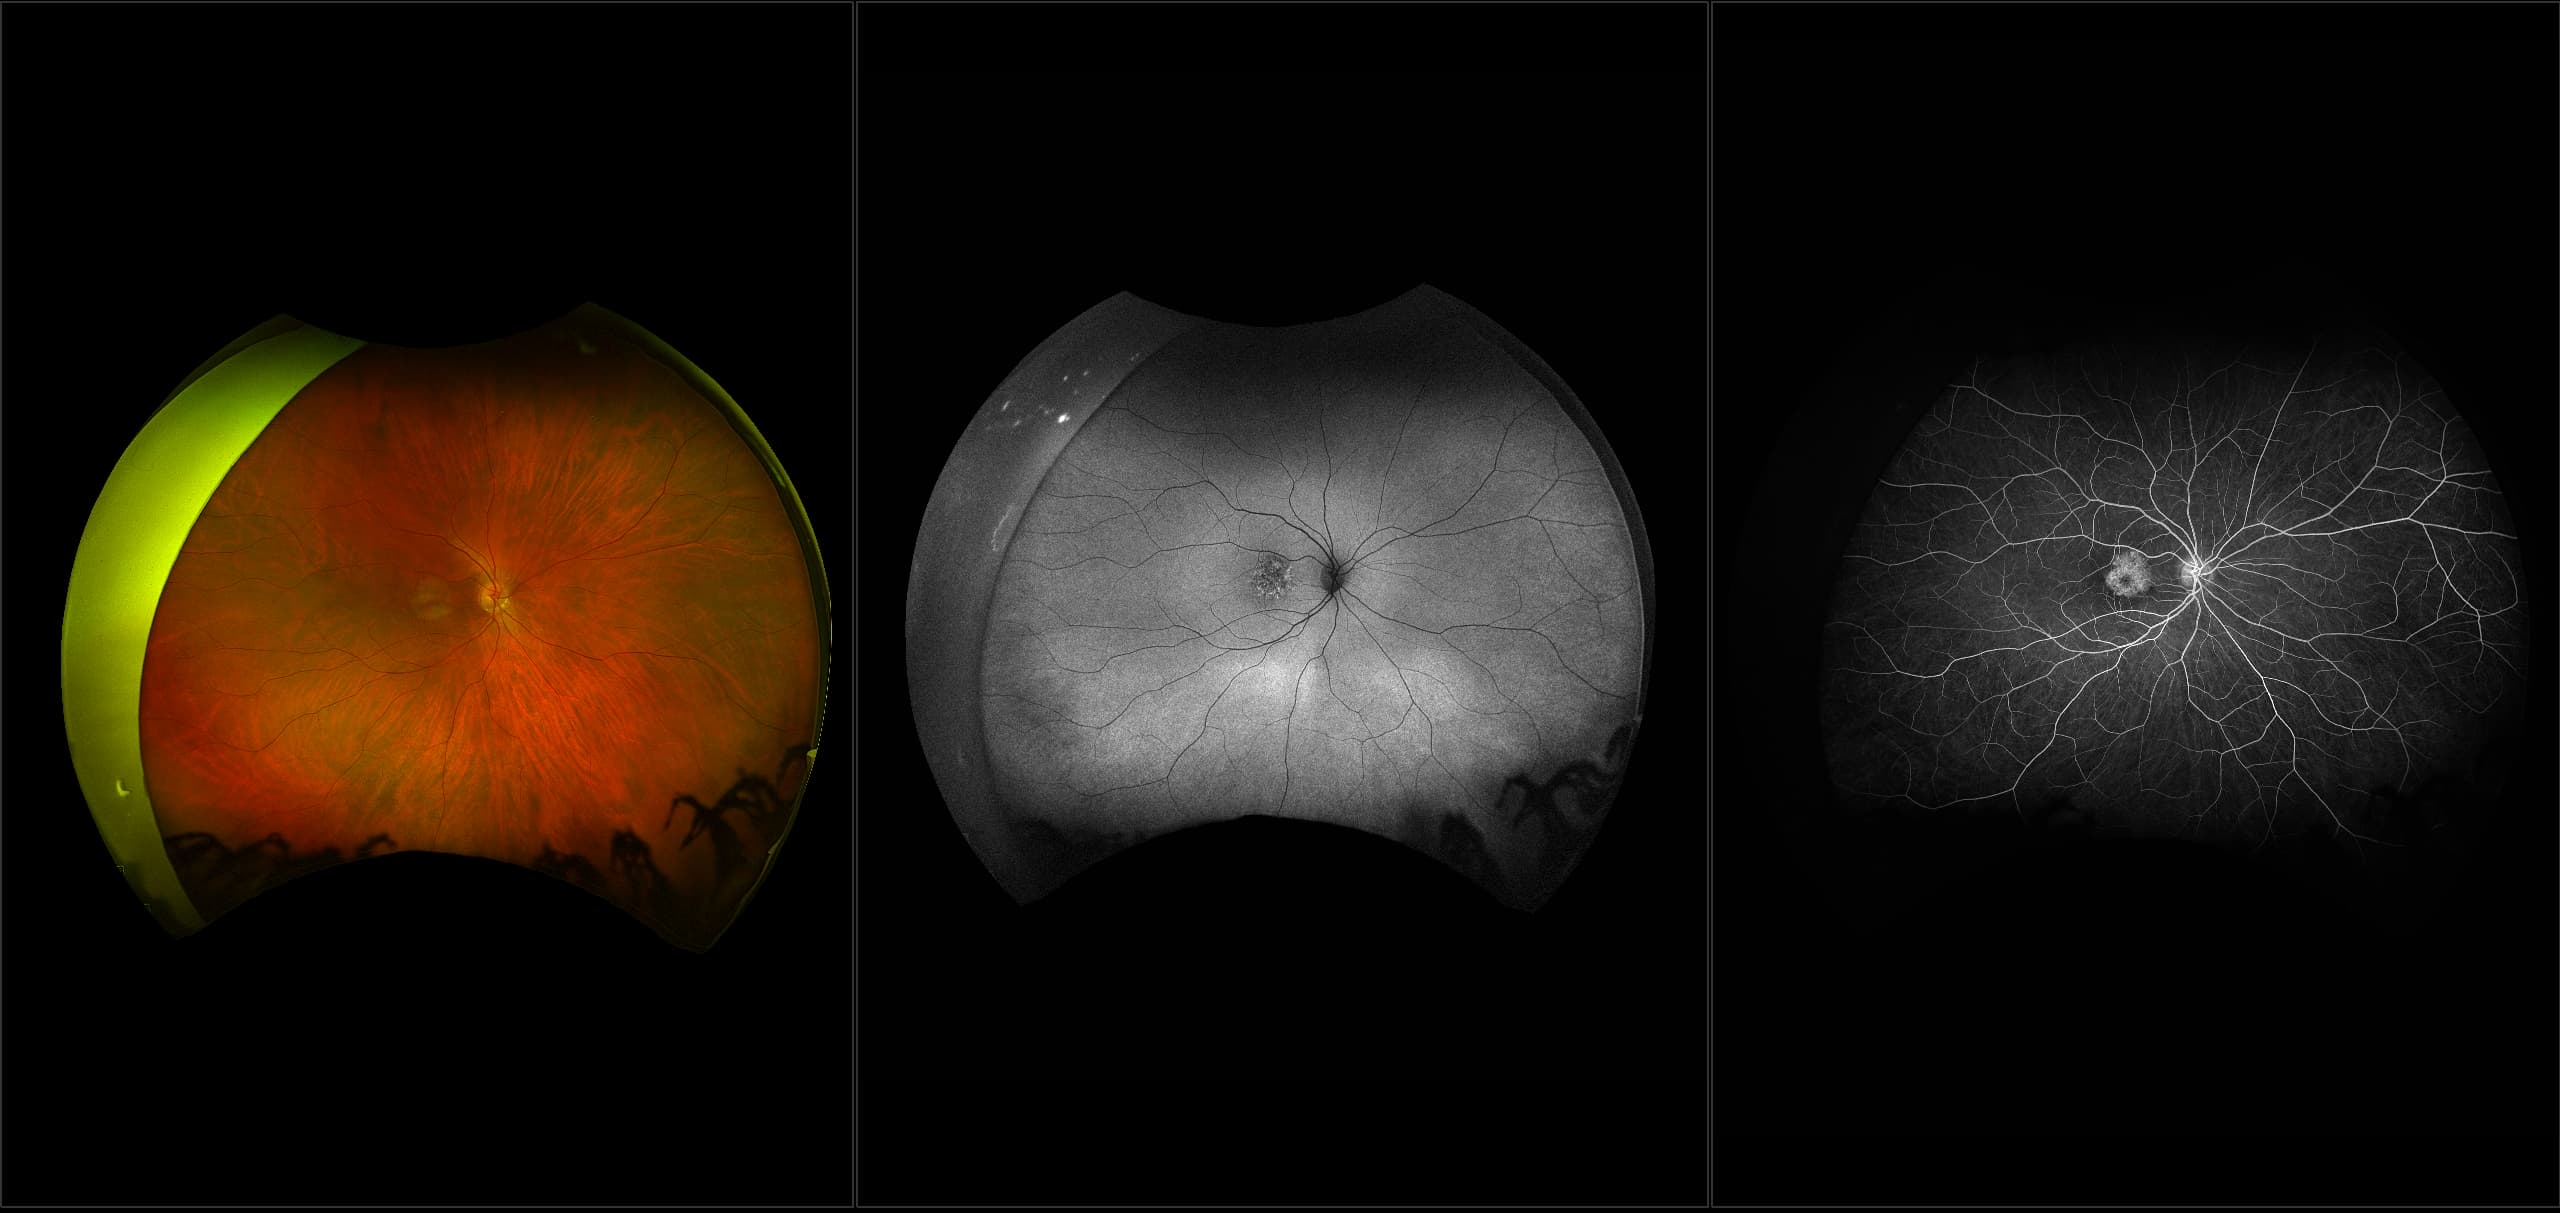

RPE hyperplasia results in a proliferation of RPE cells and thus, forms a pigmented retinal lesion which is very irregular in shape. All that is necessary is a proper stimulus to the RPE and this may be provided by physical stimulation such as vitreous traction or inflammation from infection or trauma. Sometimes a small area of this condition is called pigment clumping (gathering of RPE cells).